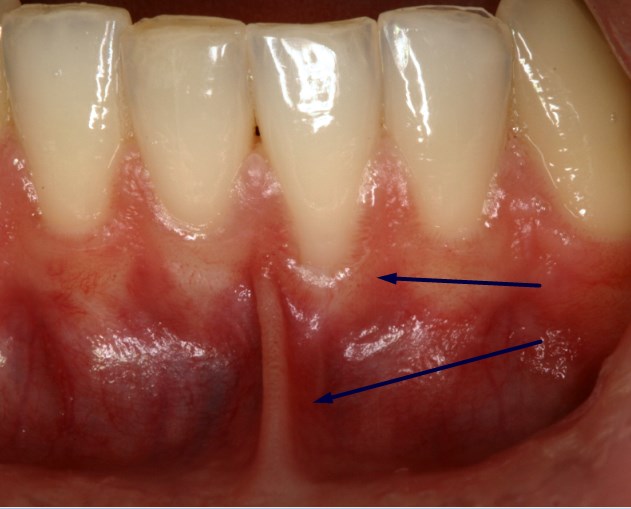

Υποχώρηση ούλου από τραυματικό βούρτσισμα

Υποχώρηση ούλου που οφείλεται σε τραυματικό βούρτσισμα